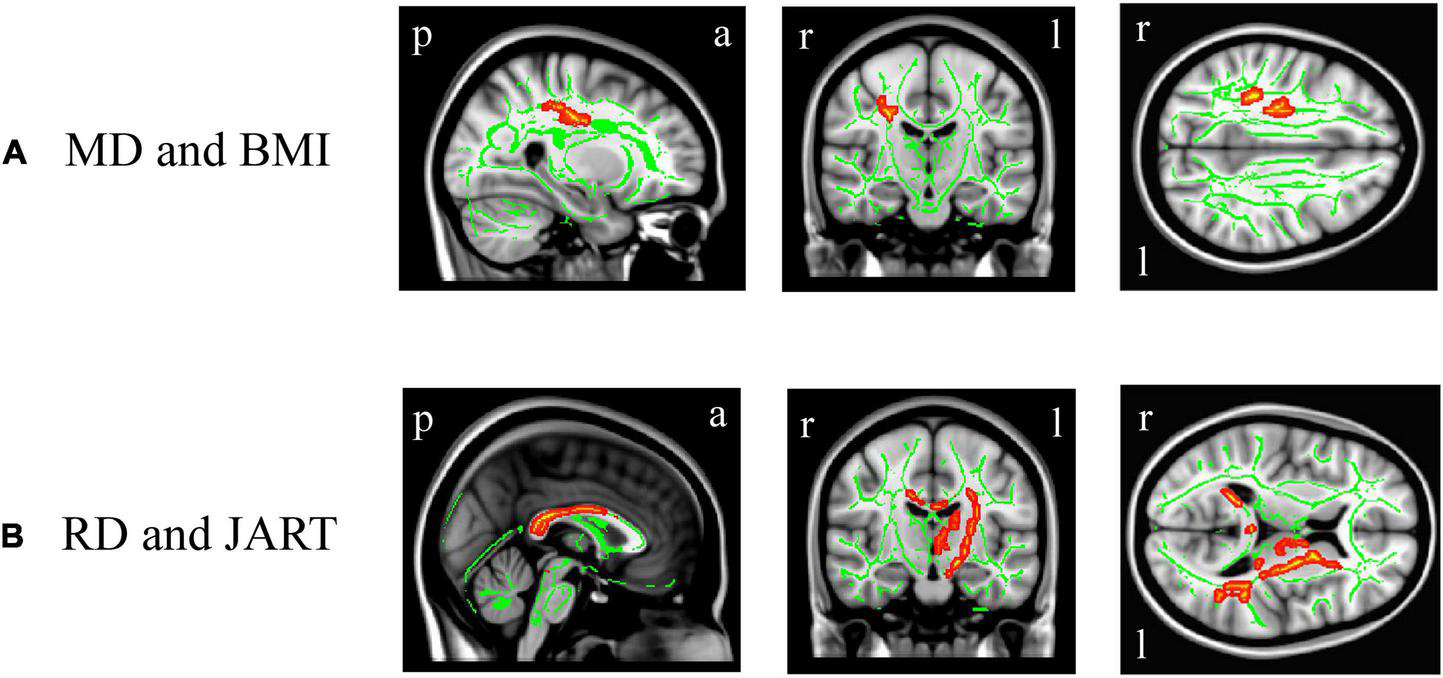

In DTI, BMI was significantly and positively correlated with the right superior longitudinal fasciculus MD value (Figure 5A, corrected p < 0.05), while there was no significant correlation between BMI and the other white matter metrics (FA, AD, or RD). There were no significant differences in the white matter metrics (FA, AD, RD, and MD values) between the underweight and non-underweight groups, the overweight or obese and underweight or normal groups, and the obese and non-obese groups (data not shown). The JART score significantly and negatively correlated with the corpus callosum and left internal capsule RD value (Figure 5B, corrected p < 0.05), while there was no significant correlation between the JART score and white matter FA, AD, or MD values.

FIGURE 5

White matter regions where the mean diffusivity (MD) and radial diffusivity (RD) values were correlated with body mass index (BMI) and Japanese Adult Reading Test (JART) score, respectively. BMI was significantly and positively correlated with the right superior longitudinal fasciculus MD value (A, p < 0.05 corrected), while the JART score significantly and negatively correlated with the corpus callosum and left internal capsule RD value (B, p < 0.05 corrected). Images coordinate x = 27.0 mm, y = −17.0 mm, z = 34.0 mm (A) and x = 0.0 mm, y = −15.0 mm, z = 10.0 mm (B), respectively, in the Montreal Neurological Institute 152 T1 atlas. a, anterior; l, left; p, posterior; r, right.